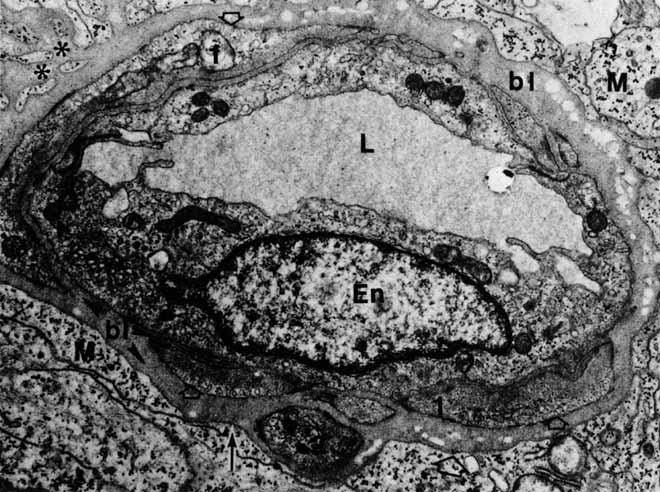

The photoreceptor outer segments have two important connections. One of these is to the inner segment, which is actually the cell body of the photoreceptor (see Fig. 21). The other connection is to the extracellular matrix that separates the photoreceptor outer segment from the pigment epithelial cell. Radioactive tracer experiments suggest that the sources of this extracellular matrix substance are the pigment epithelial and photoreceptor cells.99,100 The material, a glycoprotein consisting of chondroitin sulfate and sialic acid, is secreted into the space between the outer segments and the pigment epithelial cells by vesicles that originate in both cells. The function of this mucopolysaccharide-rich matrix is not well understood. It may provide a major route by which metabolites and nutrients pass between photoreceptor cells and their vascular supply. It may constitute the only intercellular bond between the outer segments of photoreceptors and the pigment epithelial cells, because there are no cellular connections such as tight junctions between these cells (see Fig. 23). Recent studies have identified interphotoreceptor retinol-binding protein as a major component of this matrix.100 This glycoprotein is believed to mediate the transport of a vitamin A derivative, retinol, between the photoreceptor and the pigment epithelium.

The connection of the outer to the inner segment of the photoreceptor is through a slender (0.2–0.3 μm in diameter) neck that is eccentric toward one side of the cell (see Fig. 21). The cilium, which is the embryonic basis for origin of the photoreceptors, is located in the neck and extends into the basal one third of the outer segment. It has nine pairs of microtubules. However, unlike motile cilia, the cilium has no microtubules centrally. The microtubules end in a modified centriole in the apex of the inner segment. The cilium functions as a conduit for metabolic materials going from the inner to the outer segments.

Inner Segments

The inner segment of the photoreceptor is the portion of the cell that metabolically services the outer segment. Whereas the outer segment shows high differentiation, containing only equipment necessary for the photoreceptor process, the inner segment possesses the cellular machinery essential for the metabolic and synthetic functions of the cell. There are two distinct morphologic regions in the inner segment, the ellipsoid and the myoid. The most prominent feature of the outer portion, or ellipsoid, of the inner segment is the abundance of large mitochondria at the apex (see Fig. 21). The ellipsoid appears to be more sensitive to anoxia than any other part of the photoreceptor cell.101 The staining characteristics of this area vary with the state of metabolic activity of the photoreceptor cell and may account for the subtle staining differences seen in the various types of photoreceptor cells. The mitochondria in the ellipsoid are compactly arranged. They are present in higher concentration in retinas with poor vasculature. In addition, the cones have a higher concentration and greater absolute number of mitochondria than the rods. There may be up to 600 mitochondria per cone.87 These mitochondria contain the normal enzymes for oxidative production of energy.102

The cilium or basal body arises from one of a pair of centrioles at right angles to one another in the distal portion of the ellipsoid. From the basal body originates the cross-striated fibril system of rootlets that course through the inner segment (see Fig. 21). The ciliary rootlets are composed of bundles of several hundred fibrils with a periodic alternation of light and dark zones 45 nm wide. They may extend as far as the nucleus of the cell. Their function remains speculative, although histochemical evidence suggests that they may play a role in energy or even in signal conduction. The energy-related enzyme, ATPase, has been found in the fibrils of these rootlets.103

The major protein synthetic activity and assembling of synthetic products in the inner segment take place at its proximal portion, or “myoid,” which houses the rough endoplasmic reticulum, ribosomes, and large Golgi complex associated with numerous vesicles. Because this region may be the source of the acid mucopolysaccharide in the extracellular space between the photoreceptor outer segments, disturbances of this synthetic or assembling facility could result in weakening of the normal retina-pigment epithelium adhesion. Such a defect could make this union more delicate and subject to separation in the presence of a retinal tear or exudative process originating from either the retina or the choroid.

Outer Nuclear Layer

The nuclei of the rod and cone photoreceptors form the outer nuclear layer as it is seen under light microscopy.104,105 This layer is completely internal to the external limiting membrane. Whereas cellular elements outside the external limiting membrane are arranged in a precise array with cell axes parallel to the optical system of the eye, the portions of the inner segments within the nuclear layer are arranged in a more disorderly fashion.